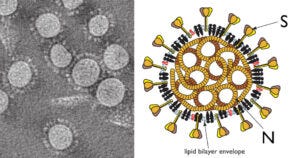

5. Coronavirus particles contain two prominent proteins: spike (S) and nucleocapsid (N)

To distinguish between infection and injection, we can again use immunohistochemistry, but this time apply it to another SARS-CoV-2 protein—namely, the nucleocapsid, which is found inside the virus particle, where it enwraps and protects the RNA genome. The rationale of this experiment is simple: cells infected with the virus will express all viral proteins, including the spike and the nucleocapsid. In contrast, the mRNA-based COVID vaccines (as well as the adenovirus vector-based ones produced by AstraZeneca and Janssen) will induce expression only of spike.